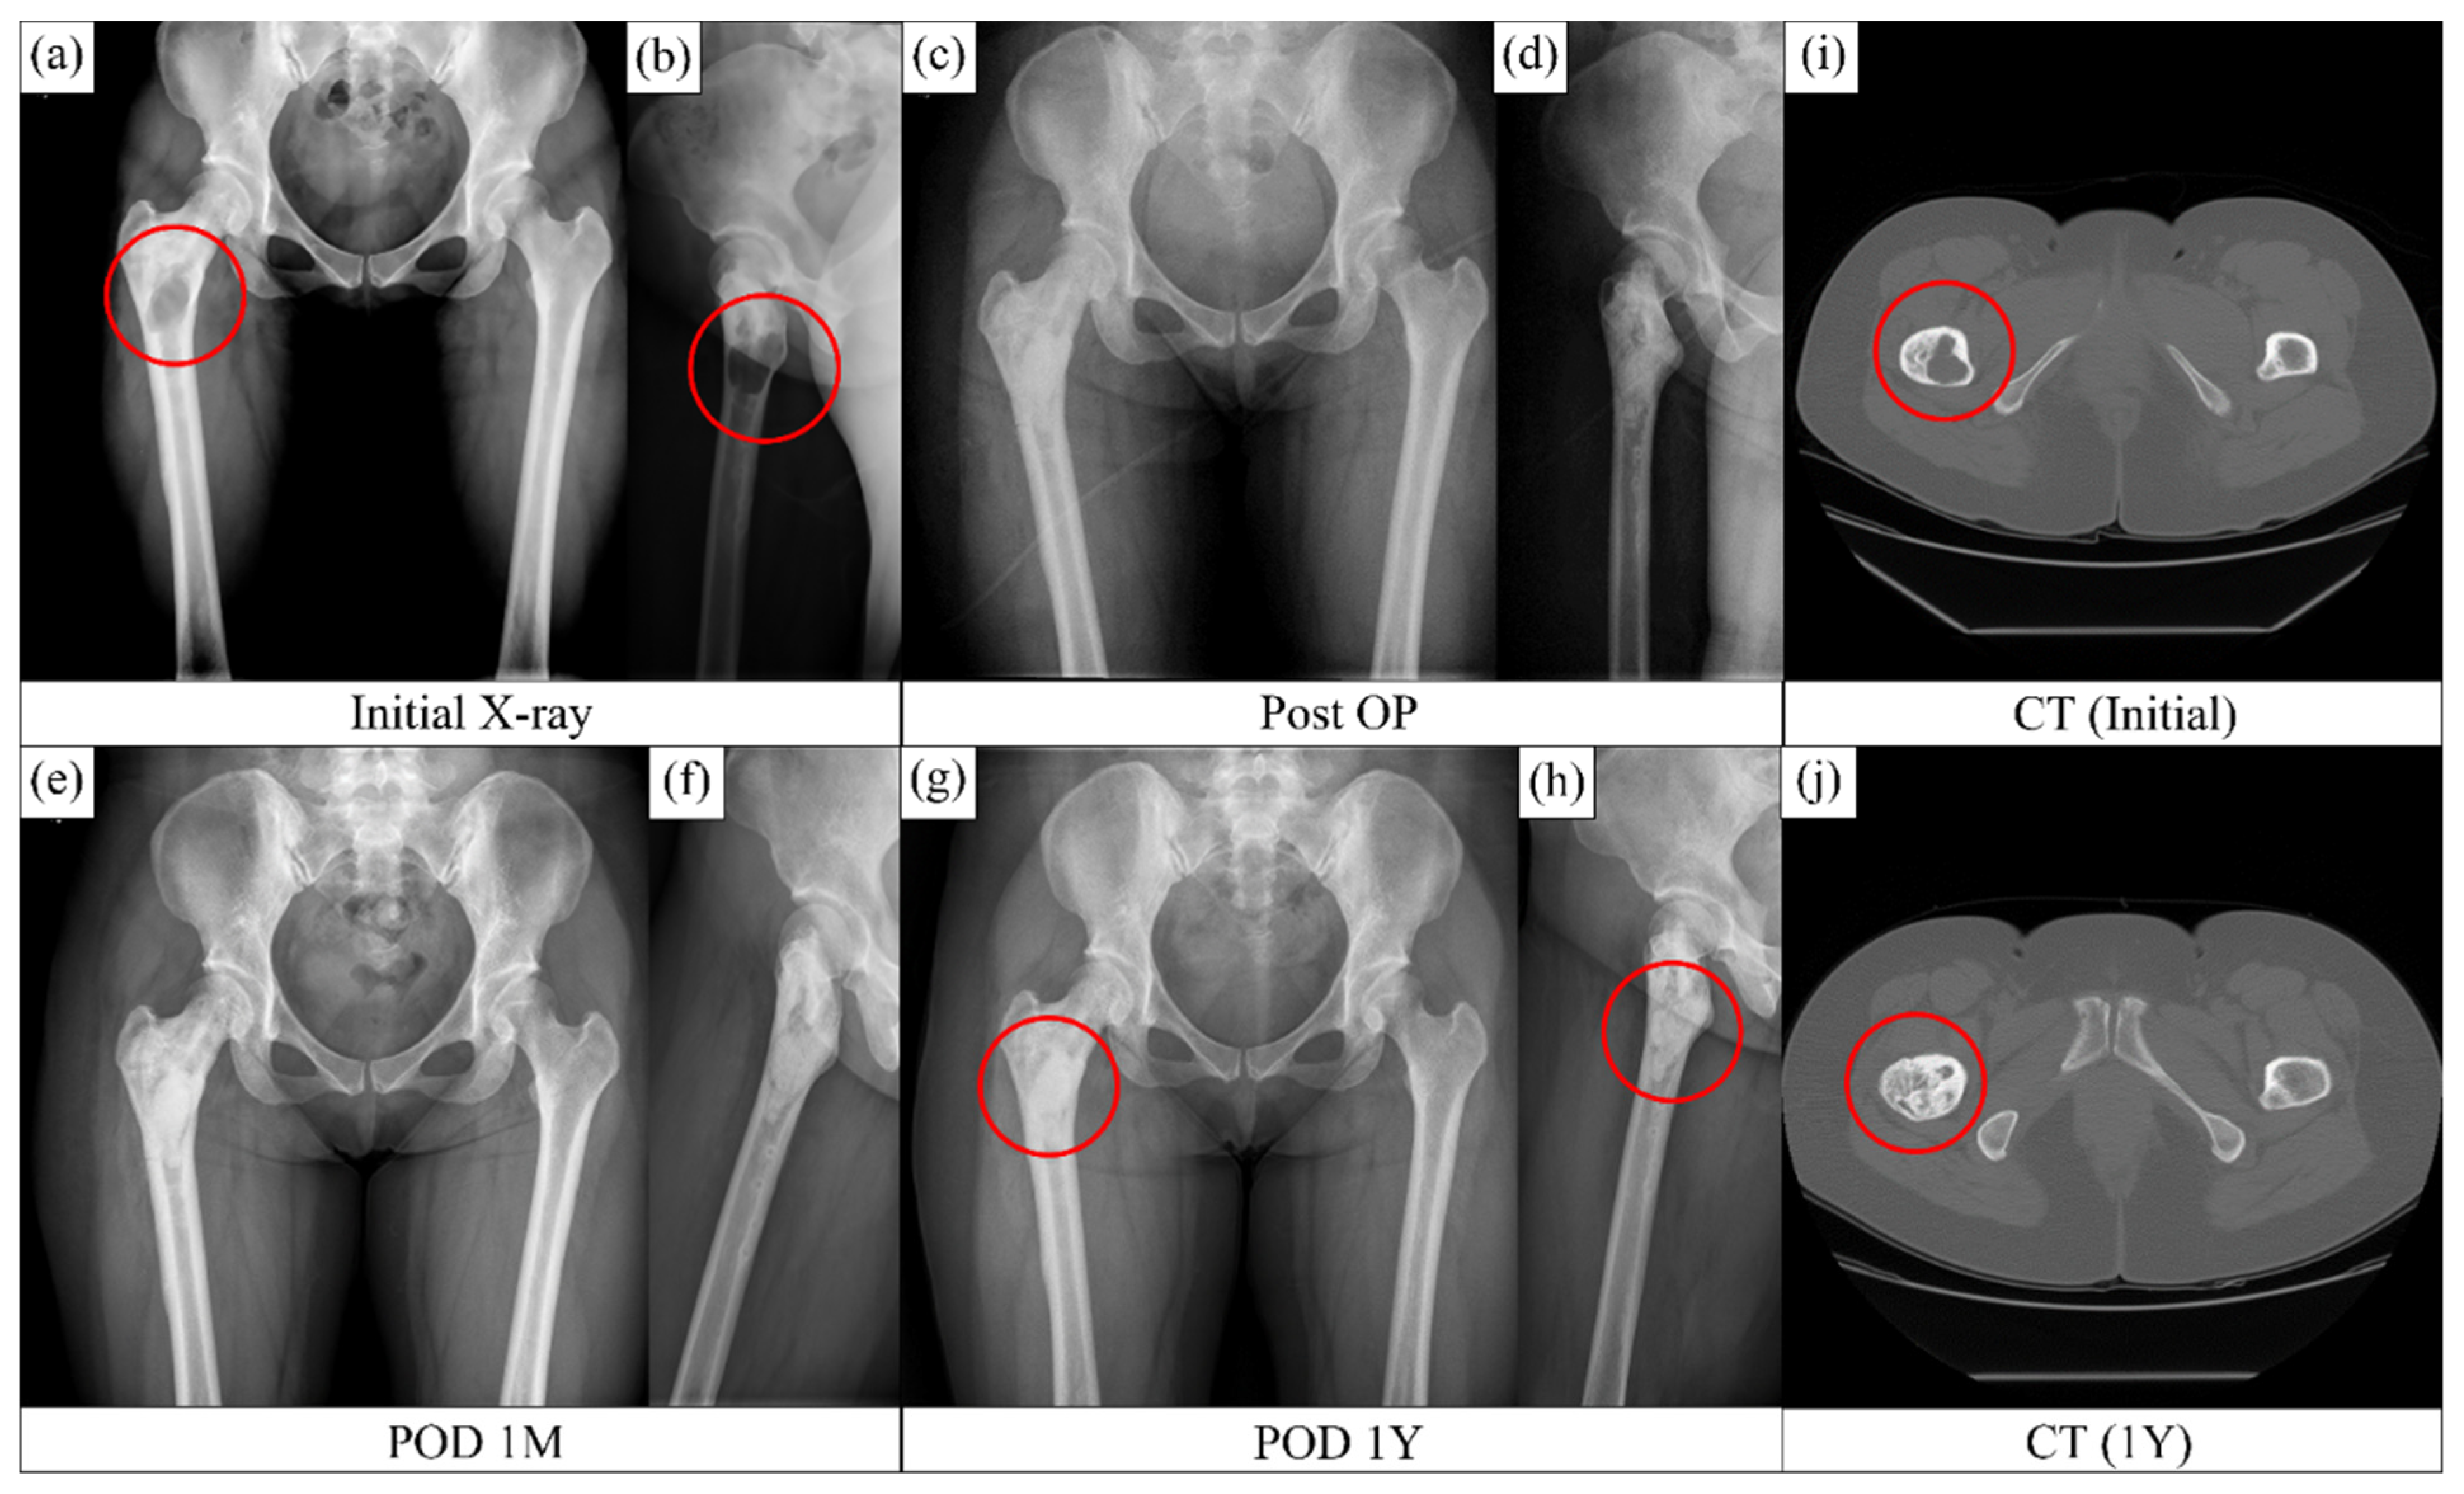

Figure 4a,b show homogeneous loss of the normal trabecular pattern based on the radiographs in the metaphysical region of the femur, with a clearly defined darker contrast appearance due to fibrous dysplasia. The medullar bone was largely replaced with fibrous tissue. Figure 4a,b,i confirm the existence of a fibrous tissue around the lesser trochanter region. Postoperative radiographs (Figure 4c,d) showed complete removal of the tissue lesion and refilling with bone substitutes. Radiographs obtained after 1 (Figure 4e,f) and 12 (Figure 4g,h) months revealed gradual recovery of the defect with bone regeneration. A homogeneous bone formation was observed throughout the whole area with dysplasia. The CT image (Figure 4j) obtained at 12 months after surgery showed an extensive bone formation and regeneration in the area that previously had fibrous dysplasia. The compact bone lining between the host bone and implant, which was visible in the radiograph, progressively faded away, thereby confirming the fusion of the original bone and the newly regenerated bone. The patient did not complain of any pain or discomfort after 1 year of treatment.

Figure 4. Bone regeneration in the bone void due to the osteofibrous dysplasia. (a,b) Preop condition, (c,d) postop condition, (e,f) after one month of operation and (g,h) after 12 months of operation. CT images of the (i) tissue lesion of the dysplasia before operation and (j) regenerated bone after 12 months postop. The red circles indicate implanted defect zone.